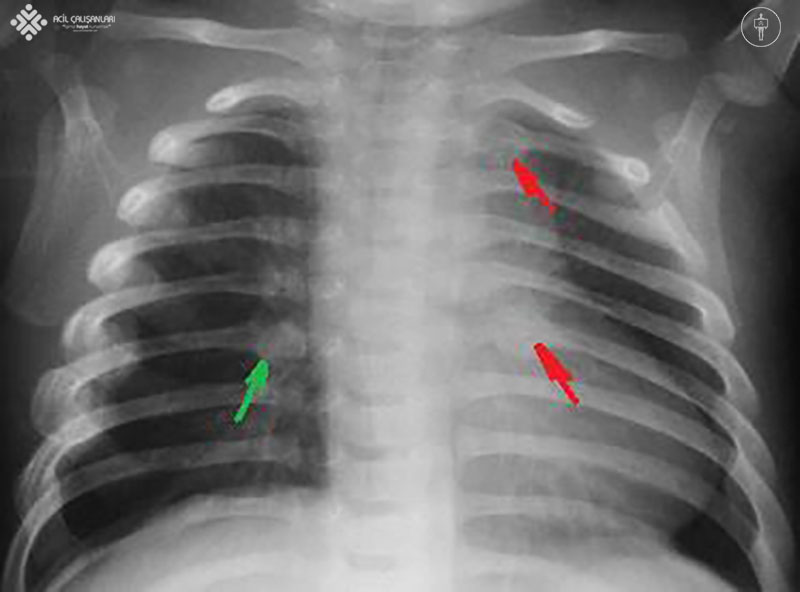

4 aylık bir kız çocuğunu annesi soluk almama nedeni ile acil servise getiriyor. Annesinden alınan mevcut hastalık öyküsünde, çocuğun 30 saniye nefes almadığını, dudaklarının maviye döndüğünü ve annesinin ağzından soluk vermesi ile nefes almaya devam ettiğini söylüyor. Anne ayrıca hastanın olaydan önce hiçbir semptomunun olmadığını belirtiyor. Çocuk anne sütüyle besleniyor ve tüm aşıları yapılmış. Fizik muayenede hasta uyanık ve ağlıyor, oksijen satürasyonu oda havasında %97 ve her iki burun deliğinde kurumuş kan mevcut. Kalp, akciğer ve karın muayenesi bulguları normal. Hastanın laboratuvar testleri normal. Çekilen beyin BT'sinde akut bulgu görülmüyor. Hastanın göğüs röntgeni aşağıda verilmiştir. Bu hasta için en olası tanınız nedir?

Hastamızın röntgen grafisinde oklarla belirtilen alanlarda yeni ve eski kırıklar görülmektedir ve burnundan kan gelmesi istismarı düşündürmektedir. Dünya Sağlık Örgütü (WHO) çocuklara yönelik kötü muameleyi, 'çocuğun sağlığına, gelişimine veya onuruna fiili veya potansiyel zarar veren her türlü fiziksel ve duygusal kötü muamele, cinsel istismar, ihmal ve sömürü' olarak tanımlamaktadır.